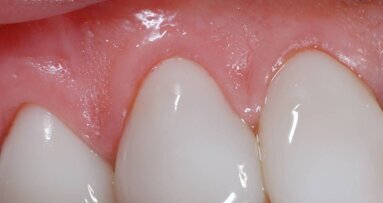

Terapie rozpoczęto od zabiegu wybielania. Następnie, w celu wyrównania układu szyjek zębowych (Ryc. 3) i pokrycia recesji dziąsła dokonano przeszczepu tkanki łącznej przy zębie 11.

Pobrano wyciski szczęki i żuchwy za pomocą jednoczasowego materiału polieterowego o średniej lepkości (Impregum Penta Soft Quick, 3M ESPE) i pełnych łyżek wyciskowych jednorazowego użytku (Position Tray, 3M ESPE). Wykonywanie wycisków nie powoduje odsłonięcia szyjek zębowych (Ryc. 4), dlatego zakładane licówki dochodzą do górnej granicy dziąsła i nigdy nie wchodzą w strefę poddziąsłową. W ten sposób zachowuje się przestrzeń biologiczną.